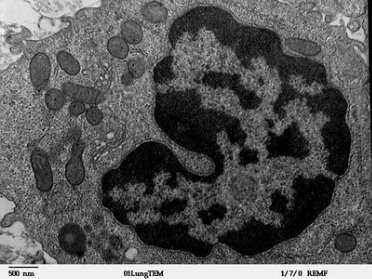

Рис. 2. Макрофаг на ультраструктурном уровне

Характерной чертой ультраструктуры макрофага является присутствие значительного количества микропиноцитозных пузырьков и лизосом, как первичных, так и вторичных. Первичные лизосомы представляют собой окруженные мембраной тельца значительной электронной плотности, содержащие гидролитические ферменты. [3, с. 112–139]

Макрофаги имеют различные размеры — от 10 до 50 мкм. Их ядра бывают разной формы — округлые, неправильной формы, с инвагинациями. На пленочных препаратах рыхлой соединительной ткани макрофаги имеют довольно интенсивно окрашенное ядро. Контур цитоплазмы неровный. В цитоплазме обычно содержатся включения и, как правило, обнаруживается зернистость — фагоцитарные частицы.